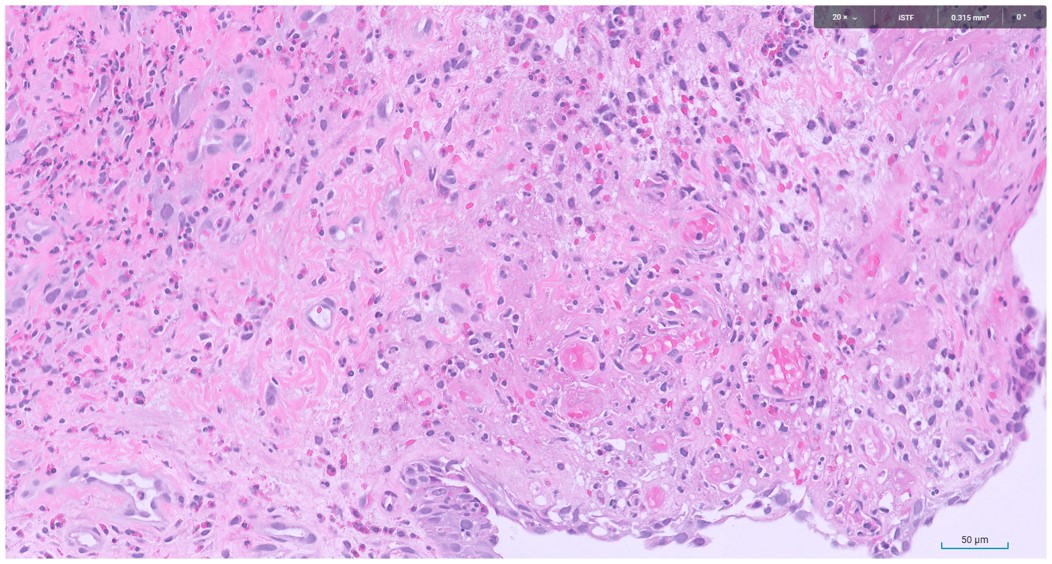

Microscopic image possibly detecting cancerous areas in human tissue